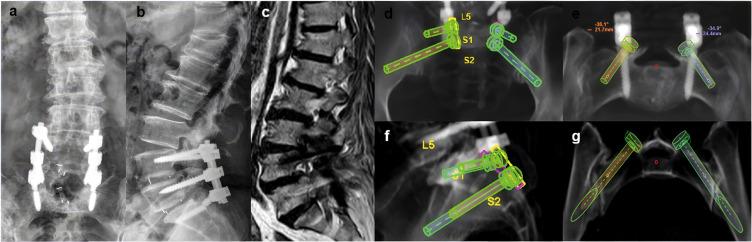

Between January 2018 and June 2022, 7 patients underwent salvage surgery with the CBT screw fixation technique assisted by the Mazor Renaissance robot system in our institution. Intraoperative observations were recorded for blood loss, duration of operation, and fluoroscopy time. Complications related to CBT screws were also recorded. The accuracy of CBT screws was recorded in accordance with the modified Gertzbein-Robbins classification. The JOA (Japanese Orthopedic Association) score for low back pain was used to evaluate surgical outcomes.

RESULTS

A total of 26 CBT screws were placed in 7 patients, including 4 females and 3 males. Three patients underwent ASD (adjacent segment disease) and four patients underwent lumbar union failure with loose or compromised PSs (pedicle screws). The mean operation time was 129.29 ± 32.97 minutes, the mean blood loss was 180 ± 52.60 mL, and the mean intraoperative fluoroscopy time was 14.29 ± 3.15 s. All screws were clinically acceptable according to the Gertzbein-Robbins classification. There were no complications related to CBT screws in any of the cases. The JOA scores for low back pain of all patients were significantly improved at the final follow-up.

The CBT screw fixation technique supplemented the traditional PS fixation technique, which can be performed as a salvage strategy for failed lumbar spine surgery and achieved good clinical results. The spinal robot was very helpful in evaluating pedicle size and determining CBT screw direction, especially in a previously instrumented lumbar pedicle.